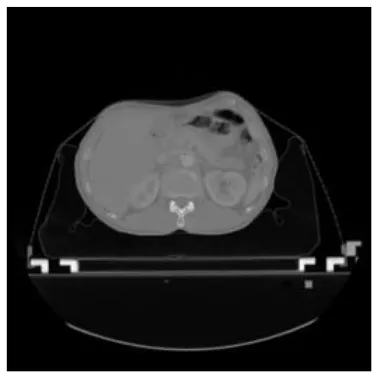

According to the acquired model parameters mentioned above, the testing set was calculated and examined. The performance of the modified algorithm for automatic organ segmentation in CT images is shown in Table 1. The organ contours segmented automatically by the algorithm were similar to those delineated by physicians manually. The model parameters including DSC, Accuracy, Recall, and Precision evaluation ones were served to evaluate the segmentation effectiveness of each organ in the validation and testing sets. In our work, the BCDU-Net CNN algorithm model was used to automatically segment different organs with the different training parameters such as epoch learning rate. The CT images which were randomly selected from the patients were put into the network model for training, and then the contours of different organs which were delineated automatically by the AI technology and manually by medical doctors were evaluated with the similarity coefficients, respectively. The results are given in Table 2. Most of the DSC values were better than 0.85 and among them the best even reached up to 0.9676. Generally, the automatic segmentation results met the requirements of clinical practice.

| Input CT image | Organs with manual segmentation | Organ with automatic segmentation | |

| Bladder | ![]() | ![]() | ![]() |

| Brainstem | ![]() | ![]() | ![]() |

| Eye-L | ![]() | ![]() | ![]() |

| Eye-R | ![]() | ![]() | ![]() |

| Femur-L | ![]() | ![]() | ![]() |

| Femur-R | ![]() | ![]() | ![]() |

| Heart | ![]() | ![]() | ![]() |

| Intestine | ![]() | ![]() | ![]() |

| Kidney-L | ![]() | ![]() | ![]() |

| Kidney-R | ![]() | ![]() | ![]() |

| Liver | ![]() | ![]() | ![]() |

| Lung-L | ![]() | ![]() | ![]() |

| Lung-R | ![]() | ![]() | ![]() |

| Mandible | ![]() | ![]() | ![]() |

| Rectum | ![]() | ![]() | ![]() |

| Spleen | ![]() | ![]() | ![]() |

| Stomach | ![]() | ![]() | ![]() |

The result of manual and automatic organ segmentation.